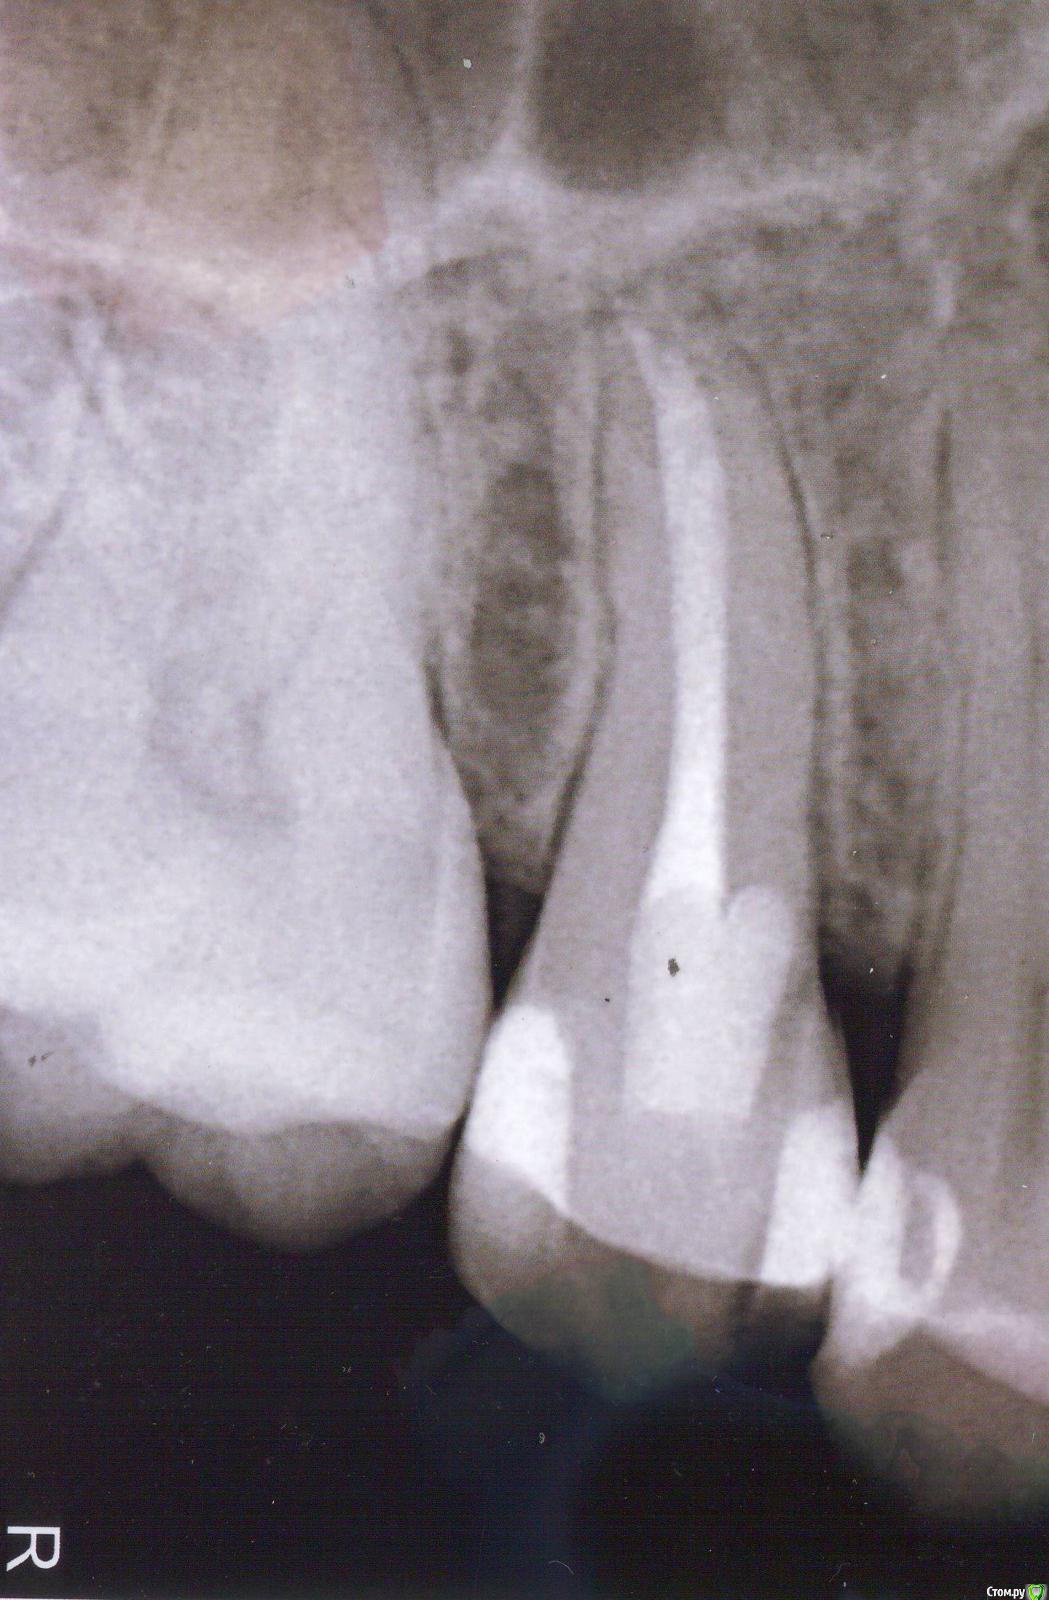

hichi Опубликовано 25 сентября, 2015 Автор Поделиться Опубликовано 25 сентября, 2015 (изменено) покажите все снимки начиная с первого Гарриевич сказал(а) 22 Сен 2015 - 00:35: покажите все снимки начиная с первого + 1 пожалуйста первичное эндо когда заболел от горячего искали доп. анатомию кальций с ложным ходом есть только один снимок, который в самом первом сообщенииесть еще один через 3 мес после лечения но он не совсем удачно сделан, думаю ничем вам не поможет Изменено 25 сентября, 2015 пользователем hichi Ссылка на комментарий

hichi Опубликовано 25 ноября, 2015 Автор Поделиться Опубликовано 25 ноября, 2015 И снова здравствуйте! 1. Плюс к вышеперечисленным симптомам появилась боль при накусывании, но не всегда а только если что-то мелкое и жесткое типа крошки от сухаря или косточки попадает на зуб. И только в одной точке - где-то у основания бугров, 14 или 15 точно не могу определить. Как куснешь сразу резкая боль и инстинктивно сразу зубы разжимаешь, точно не успеваю отследить но кажется что 14-й.На 14-м пломба сделана около года назад, около полугода назад частично скорректирована в районе контакта 14 и 15, зуб живой.С 15-м ничего не изменилось, все тоже самое что и в сообщениях выше. 2. Почему-то не растет сосочек пострадавший при реставрации контакта 14 и 15 полгода назад. Контакт нормальный - точечный и плотный, нить щелкает, по снимку уровень кости тоже в норме и перфорации и трещины 15-го тоже вроде как нет. Что может быть? 3. В 15-м не слишком ли тонкая стенка в том месте где не совсем удачно искали каналы, не треснет ли зуб от нагрузки? Имеет ли смысл делать вкладку или коронку и если да то изкакого материала с учетом того что противоположные зубы абсолютно здоровые? И если делать вкладку это же надо зуб снова сверлить, толщина стенки там осталась 0,32 мм не будет ли перфорации? Спасибо. Ссылка на комментарий